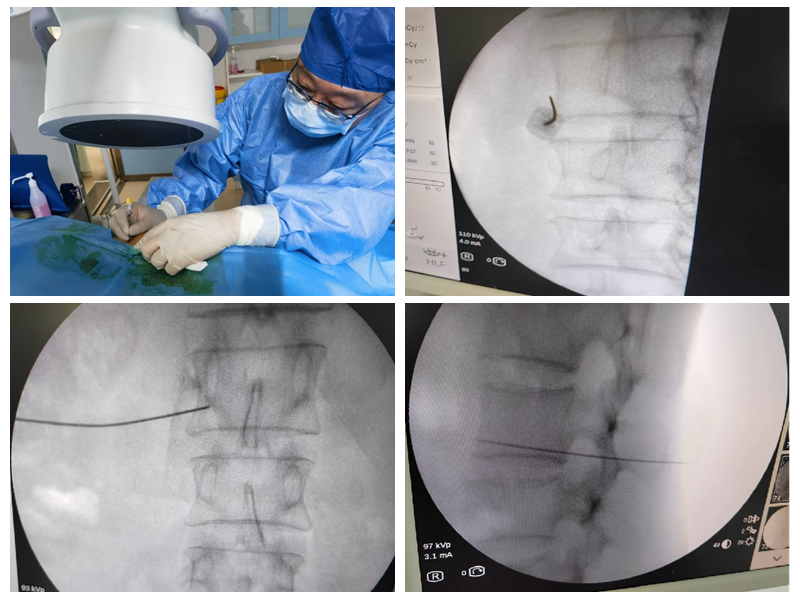

能完成该标准要求的绝大多数手术,包括选择性神经根阻滞技术、交感神经丛(干)介入医治技术、颅神经介入医治技术、神经射频调制技术、腰椎间盘介入医治技术、颈椎间盘介入医治技术、外周神经射频技术、脊髓电刺激、椎体成形术、硬膜外造影术、椎间盘造影术等。

选择性神经根阻滞技术